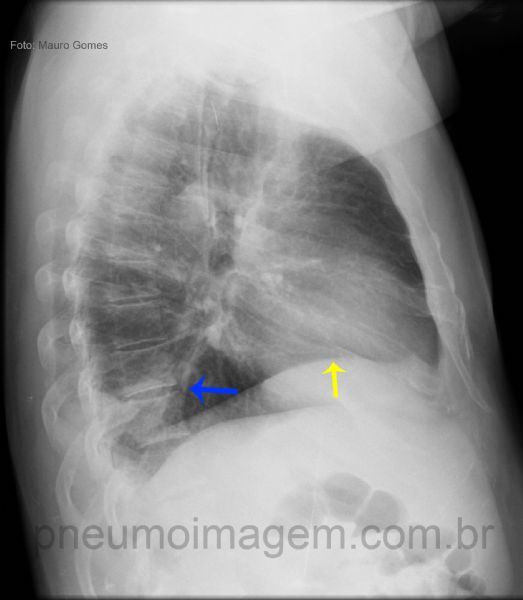

Ao perfil pode-se observar que existe uma elevação da cúpula frênica direita (seta amarela) associada a uma área triangular com a base voltada para a coluna (seta azul), compatível com uma atelectasia segmentar em lobo inferior direito.

In the side view we observe that there is an elevation of the right diaphragm (yellow arrow) associated with a triangular area with the base turned to the column (blue arrow), consistent with a segmental atelectasis in the right lower lobe.